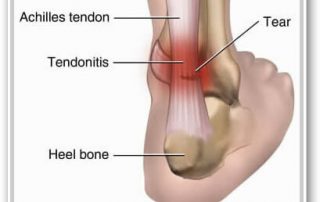

Achilles Tendon Injuries

Dr. Allen I was hoping you could help me with my Achilles Tendon Injury! See my history below. I've had a very long-standing Achilles Tendon Injury (since April 2012), coinciding with a piriformis/gl [...]